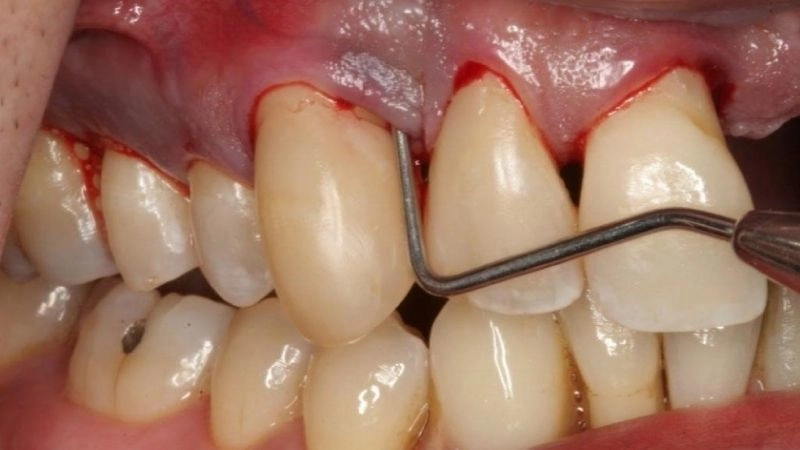

Nhiều trường hợp cao răng tích tụ nhiều và lan xuống ở phần dưới nướu. Bởi vậy, việc lấy cao răng ở phần này sẽ gây chảy máu. Tình trạng chảy máu là hoàn toàn bình thường và không có gì đáng lo lắng khi được xử lý đúng cách. Tuy nhiên, nếu vùng chảy máu ở nướu không được xử lý kịp thời thì sẽ gây ra viêm nhiễm, lan rộng vào sâu vào vùng nha chu, gây những biến chứng nguy hiểm, thậm chí là rụng răng.